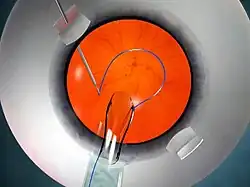

The glued IOL technique consists of making two partial-thickness, approximately 2.5 mm by 2.5 mm, scleral flaps exactly 180° apart, followed by a sclerotomy with a 20-gauge needle 1 mm from the limbus. A 23-gauge vitrectomy cutter is introduced from the sclerotomy site, and a thorough vitrectomy is done to remove all the vitreous tractions. A corneal tunnel is fashioned, then a 23-gauge glued-IOL forceps is passed through the sclerotomy site, and the tip of the leading haptic of the IOL is grasped, which is then externalized and brought out onto the ocular surface (Fig 3). Similarly the trailing haptic is then externalized using the "handshake technique". Scleral pockets are made at the edge of the flap with a 26-gauge needle just parallel to the sclerotomy site, into which the two haptics are then tucked for additional stability (Fig 4). The scleral flaps are then glued back into place using biological glue. The IOLs that can be used are the three-piece foldable IOLs with slightly firm haptics, or a three-piece non-foldable IOL. The glue is then used to seal the conjunctival closure.